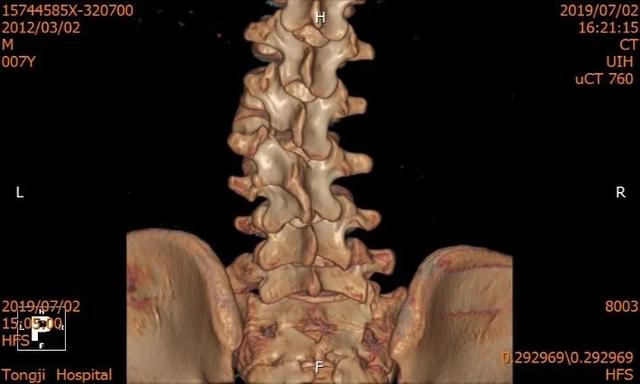

经多方打听,家人带着小徐同学慕名找到了上海市同济医院程黎明院长带领的脊柱外科团队。程院长带领的脊柱外科团队,围绕「微创-再生-重建」理念,在脊柱生物力学及生物学再生重建方面把握国际最新前沿动态。经过科室病情讨论,仔细评估病情,发现患儿是腰 2 先天性半椎体畸形,已经引起整个腰椎的侧弯畸形加后凸畸形,认为患者手术指征非常明确,亟需接受脊柱半椎体畸形切除短节段矫形手术治疗,否则整个脊柱畸形会更加明显,甚至影响心肺内脏的发育,治疗难度也会更大。「脊柱半椎体畸形矫形手术可以阻断畸形进展,有效恢复脊柱的生物力学结构,可以让患者挺直胸膛,回归正常生活。」小徐同学及家人欣然接受了程黎明院长脊柱外科团队的手术方案。

医疗团队本着对少年儿童的关爱,把担子压在自己肩上,准备得仔细又仔细。术前还以患者畸形脊柱的超薄 CT 为基础,运用最先进的 3D 打印技术构建了患者脊柱模型,并利用数字模拟技术模拟了患者内固定的最佳植入路径,反复模拟手术,做好了充分的术前准备。

术前 CT & 3D 打印